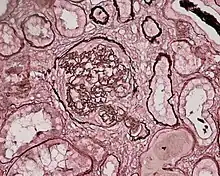

Photomicrograph of a kidney biopsy from a person with crescentic glomerulonephritis showing prominent fibrocellular crescent formation and moderate mesangial proliferation in a glomerulus. Hematoxylin and eosin stain.

Rapidly progressive glomerulonephritis

Crescentic glomerulonephritis induced by infective endocarditis on PAS staining and immunofluorescence. PAS staining (left) demonstrated circumferential and cellular crescent formation with interstitial nephritis. Immunofluorescence (right) demonstrated C3 positive staining in mesangial area.

Photomicrograph of renal biopsy showing crescent formation and tuft narrowing. Periodic acid silver methenamine stain.

Rapidly progressive glomerulonephritis, also known as crescentic GN, is characterised by a rapid, progressive deterioration in kidney function. People with rapidly progressive glomerulonephritis may present with a nephritic syndrome. In management, steroid therapy is sometimes used, although the prognosis remains poor.[9] Three main subtypes are recognised:[4]:557–558

Histopathologically, the majority of glomeruli present "crescents". Formation of crescents is initiated by passage of fibrin into the Bowman space as a result of increased permeability of glomerular basement membrane. Fibrin stimulates the proliferation of endothelial cells of Bowman capsule, and an influx of monocytes. Rapid growing and fibrosis of crescents compresses the capillary loops and decreases the Bowman space, which leads to kidney failure within weeks or months.